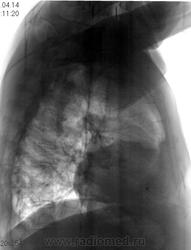

Не ясный...  В клинике превалирует одышка...

Отмечает внезапно возникшую одышку? ЭХО-КГ было? Мне чудится симптом Вестермарка в верхней доле справа и нежная интерстициальная инфильтрация в S6 справа. Хвост правого корня не красивый, может он "обрублен"? Ну и признаки ХОБЛ есть.

Плевральные наложения справа, пока больше ничего плхого не вижу

Тень сердца объясняет причину одышки.

Коллеги, а как Вы объясните эту тень? Что-то я на ней зависла. Не ателектаз, не междолевой плеврит. Абдоминомедиастинальная липома?

Тень это жир, по прямому тоже хорошо видно что сердце жирновато

Попробую объяснить. Стрелок на картинках не нарисую, по причине что я сейчас однорукая (отдыхаю на больничном со сломаной правой). Я не настаиваю на своем мнении, мне только "почудилось". Если сравнивать лег рисунок верхних долей, то справа он мне кажется обедненным. Для такого-то сердца и сосудов по лег полям должно быть поболее. А интерстиц инфильтрация, потому что нет "пятен" и "хлопьев" сливающейся альвелярной (простите КТ-шный термин), а есть нежное сетчатое затемнение, на фоне которого прослеж сосуды. Вот дисковидных коллапсов я не нашла, покажете?

Насчет ХОБЛ - стенки бронхов утолщены муфтой, хрящевые кольца трахеи, главных, долевых и устьев сегментарных кальцинированы, это отлично видно на линейках.

У такого человека в возрасте мне кажется сейчас важнее всего как раз исключить ТЭЛА, ХОБЛ и застой это меньшее из зол.

Как-то сомневаюсь я в абдоминомедиастинальной липоме. Огроменные размеры, фестончатый контур. Подумала ещё о парастернальной диафрагмальной грыже. Валентин Львович, а в архиве что?